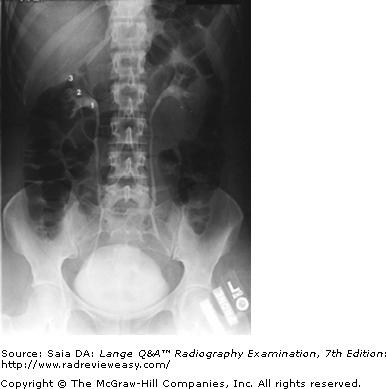

In which of the following positions was the radiograph in Figure A taken?

A RPO

B LPO

C AP axial

D Right lateral decubitus

-The pictured radiograph is an oblique position of the large bowel, illustrating an "open" view of the hepatic/right colic flexure and ascending colon, with the splenic/left colic flexure superimposed on the descending colon. Therefore, the radiograph must have been made in either an RAO (if the patient was prone) or an LPO (if the patient was supine) position. The LAO and RPO positions are used to demonstrate the splenic/left colic flexure and descending colon free of self-superimposition. AP or PA axial is generally used to visualize the rectosigmoid colon.